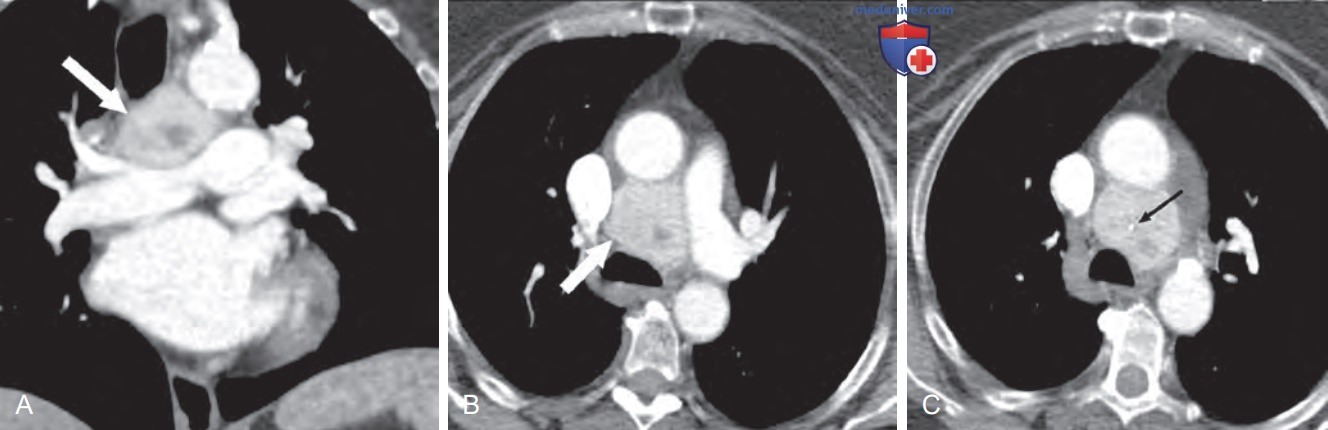

Опухоли могут захватывать изотоп при сцинтиграфии с метайодбензилгуанидином. При КТ и МРТ они характеризуются ярким контрастным усилением (рис. ниже).

Фронтальная (А) и аксиальная (B) реконструкции из серии томограмм сердца, на которых видно накапливающее контраст неоднородное образование (белая стрелка) между основанием легочной артерии и аортой — в типичном для параганглиомы месте. (C) На аксиальной реконструкции (срез сделан выше, чем на рисунке B) видна точечная кальцификация в толще опухоли (черная стрелка)